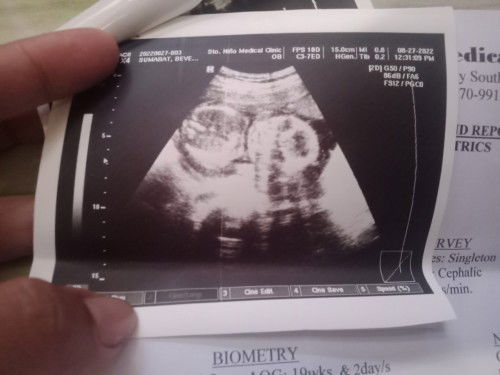

Hello mga mommies last Saturday nagpa ultrasound ako and I'm 20 weeks and 1 day pregnant na. Then I found out that yong placenta ko low laying pala so nasa unahan yong placenta ko sa cervix ko si baby nasa likod na. May chance pa po ba na mapunta sa likod yong placenta ko? May possibilities po ba na ma CS ako if ever nasa unahan pa rin siya? Sa mga mommies po jan na may same case sakin what are the Do's and Dont's po sa mga pregnant moms na may low laying placenta(placenta previa)#pleasehelp #advicepls #pregnancy